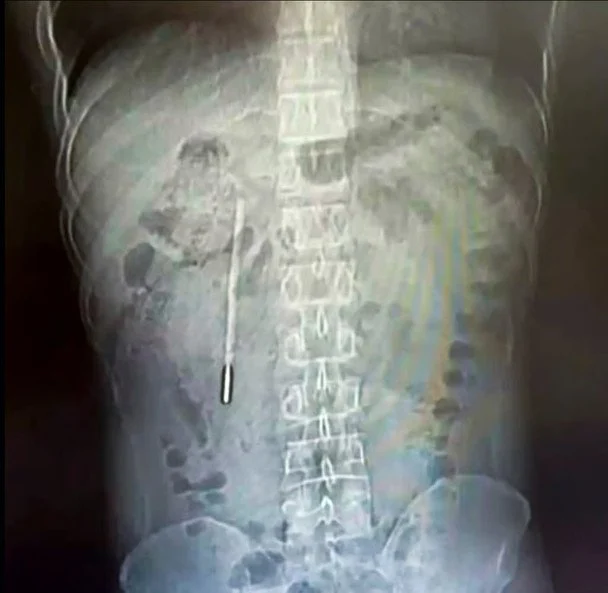

У Китаї хірурги видалили з тіла пацієнта ртутний термометр. Чоловік жив зі стороннім предметом у тілі з підліткового віку. Про це розповідає «Главком» із посиланням на South China Morning Post.

32-річний чоловік звернувся до лікарні у місті Веньчжоу, провінція Чжецзян (Китай) зі скаргами на біль у шлунку. Як з'ясувалося, ще у 12 років він проковтнув термометр. Підліток не розповів нікому про цей інцидент, оскільки боявся реакції батьків.

Однак через 20 років біль у кишківнику нагадала йому про це. Тож медики лікарні Веньчжоуського медичного університету провели обстеження та виявили сторонній предмет у дванадцятипалій кишці пацієнта.

Ситуація була критична, оскільки кінчик термометра притискався до стінки кишківника. Це могло викликати внутрішню кровотечу та перфорацію (розрив цілості стінки порожнистого органу, як, наприклад кишківника, – «Главком»).

Попри складність операція тривала 20 хвилин. Водночас розташування термометра було небезпечним, але хірургам вдалося видалити його з тіла чоловіка. За словами лікарів, ртуть не потрапила в організм, а позначки на термометрі майже вицвіли.